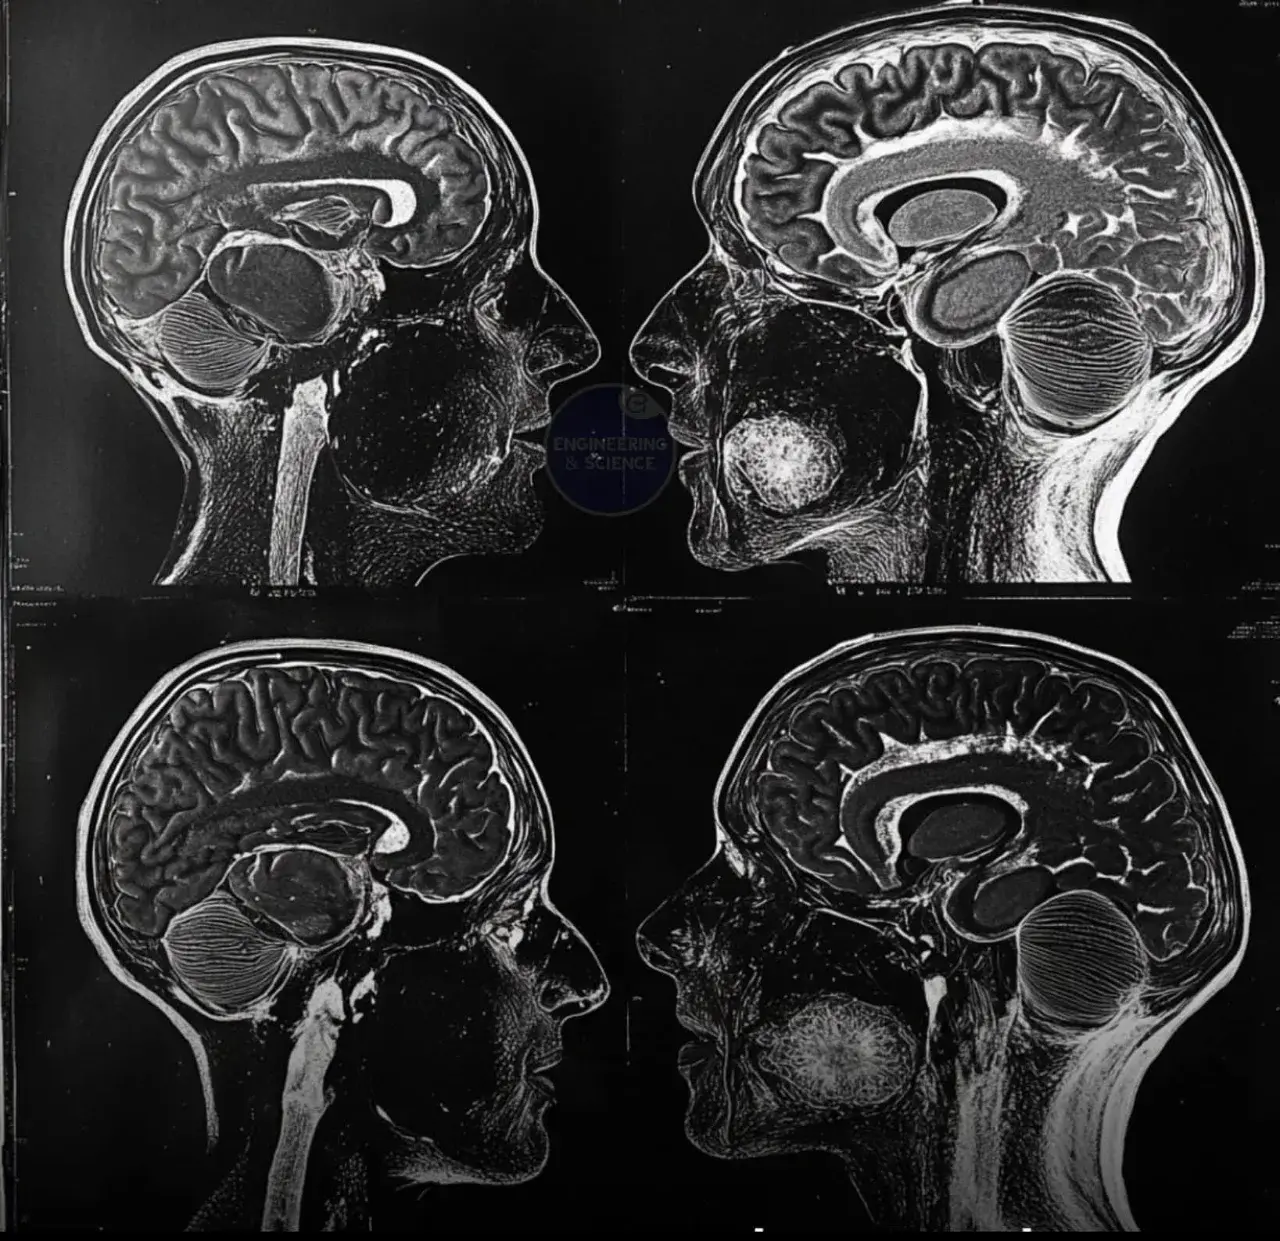

ในโลกที่เทคโนโลยีทางวิทยาศาสตร์ก้าวหน้าไปอย่างไม่หยุดยั้ง การศึกษาที่เกี่ยวข้องกับสมองได้เผยให้เห็นถึงผลกระทบที่น่าทึ่งของการอดอาหารต่อระบบประสาท ด้วยการใช้เทคโนโลยีสแกนสมองขั้นสูง นักวิจัยสามารถสังเกตการเปลี่ยนแปลงของสมองเมื่อร่างกายเข้าสู่สภาวะอดอาหาร และพบว่ากระบวนการนี้ช่วยเพิ่มความยืดหยุ่นทางประสาท สมรรถภาพทางการรับรู้ และความกระจ่างแจ้งของจิตใจได้อย่างน่าทึ่ง

การอดอาหารกระตุ้นให้สมองเกิดการเปลี่ยนแปลงทางโครงสร้างและหน้าที่ โดยมีผลต่อกระบวนการที่เรียกว่า neuroplasticity หรือความสามารถของสมองในการปรับตัวและสร้างเครือข่ายเส้นประสาทใหม่ การเปลี่ยนแปลงเหล่านี้ส่งผลโดยตรงต่อการลดความเสี่ยงของโรคทางระบบประสาท เช่น อัลไซเมอร์และพาร์กินสัน โดยการส่งเสริมการสร้างเซลล์สมองใหม่ (neurogenesis) และกระตุ้นการทำงานของโปรตีนที่เกี่ยวข้องกับการปกป้องเซลล์ประสาท นอกจากนี้ การอดอาหารยังช่วยลดการอักเสบของสมอง ซึ่งเป็นปัจจัยสำคัญที่เกี่ยวข้องกับโรคทางระบบประสาทหลายประเภท

นอกเหนือจากผลกระทบเชิงสรีรวิทยาแล้ว การอดอาหารยังเป็นปัจจัยที่ช่วยเสริมสร้างศักยภาพของจิตใจ ผู้ที่อดอาหารเป็นประจำมักรายงานว่าพวกเขามีสมาธิที่ดีขึ้น ความคิดกระจ่างขึ้น และสามารถจดจำสิ่งต่างๆ ได้ดีขึ้น ซึ่งอาจเกิดจากการที่ร่างกายเข้าสู่ภาวะ ketosis หรือภาวะที่ร่างกายเผาผลาญไขมันเป็นพลังงานแทนน้ำตาล กระบวนการนี้ไม่เพียงแต่ช่วยให้ร่างกายทำงานอย่างมีประสิทธิภาพ แต่ยังช่วยให้สมองได้รับพลังงานที่บริสุทธิ์และสม่ำเสมอมากขึ้น